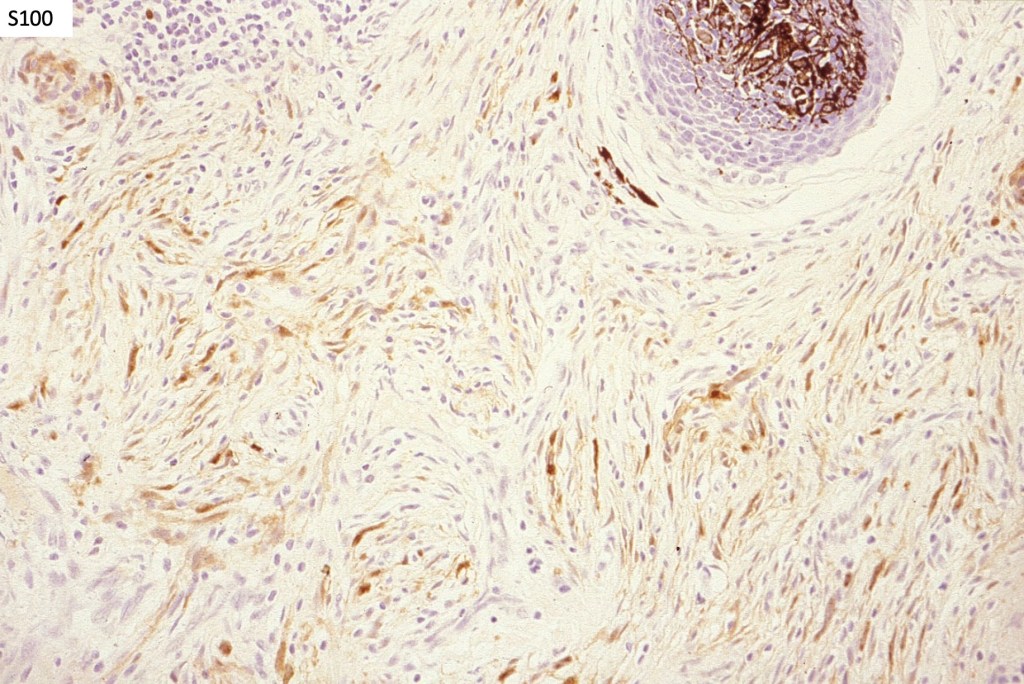

Neurocristic hamartoma

This is exceedinly rare and represents a hamartomatous lesion of neural crest origin The scalp is most often affected but although it can also present on the face, neck, buttock and elsewhere. It presents as folliculocentric brown or blue/black papules and nodules sometimes associated with alopecia. Exceptionally melanoma supervenes.

Histologically it presents in varying proprtions of banal and blue nevus accompanied by scattered dendritic cells associated with neurofibroma-like spindle cells and Schwann cell nodules with Meissner corpusces surrounded by sustentacular EMA positive cells. The lesion typically ensheathes the hair follicles.